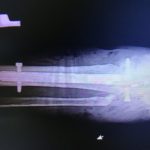

rtg po operacji